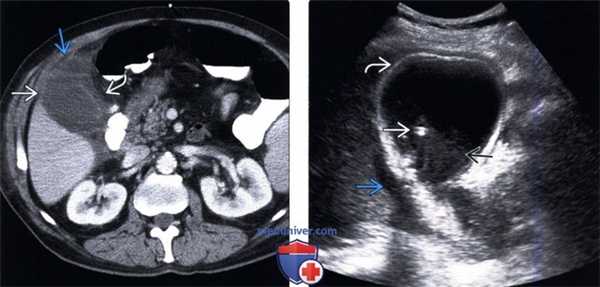

(Левый) При КТ с контрастным усилением у пациента с острым бескаменным холециститом визуализируются растянутый желчный пузырь с утолщенной стенкой, скопление перипузырной жидкости и воспаление перипузырной жировой клетчатки. Обратите внимание на слабое контрастирование стенки в области дна желчного пузыря.

(Правый) На поперечном УЗ срезе у пациента с бескаменным холециститом определяется сладж, утолщение стенки и чрескожный холецистостомический дренаж. Также видно скопление перипузырной жидкости.